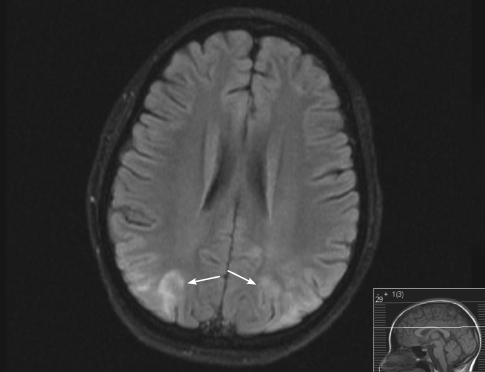

Encephalopathy Syndrome

<p class="p1">An 11-year-old girl being treated for renal failure and hypertension was found unresponsive at home in bed after a generalized seizure that, according to the child’s...